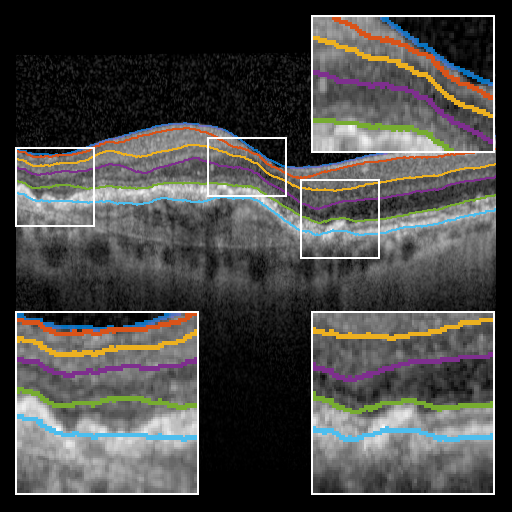

Refer to caption

Figure 3: Qualitative comparison of each segmentation approach. Top row, left to right: ground truth, BRU-net, U-net; bottom row, left-to-right: Dufour et al., Chen et al., Mayer et al. Only BRU-net is able to segment the BM layer under the pathological region. The smaller receptive field of U-net results in discontinuities. Further qualitative results are provided in the supplementary material.

To evaluate BRU-net, we compare it with the 3D methods of Dufour [5], Chen et. al. [4], and the 2D method of Mayer et. al. [12] on the same dataset. Additionally, we train a traditional U-net configuration [14] using the procedure described above. Fig. 3 provides a qualitative comparison of the results.